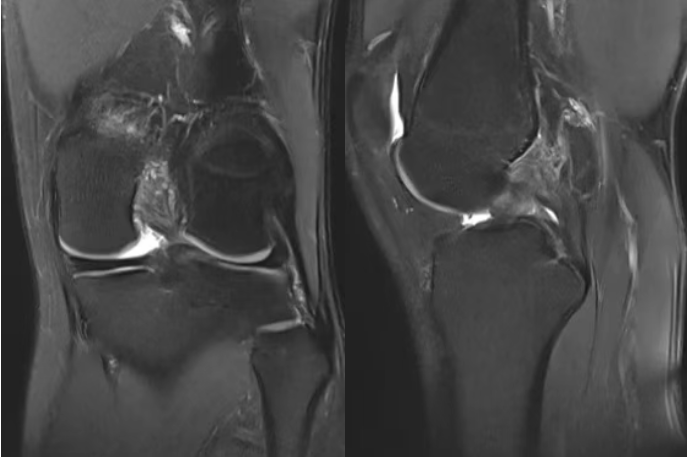

后交叉韌帶位于膝關(guān)節(jié)最深部,起自股骨內(nèi)髁外側(cè)面前部,向后下方延伸,止于脛骨平臺(tái)后方斜坡。該韌帶比前交叉韌帶更粗大和強(qiáng)壯。

后交叉韌帶的主要功能是抵抗脛骨后移,作為防止小腿骨相對(duì)于大腿骨向后錯(cuò)位的最主要結(jié)構(gòu),在上下坡、下樓梯和減速奔跑時(shí)起著關(guān)鍵的穩(wěn)定作用。

PCL(后交叉韌帶)損傷通常需要較大暴力導(dǎo)致,常見于:

1. “儀表盤損傷”:最常見的損傷機(jī)制。車禍中,乘員屈曲的膝蓋猛烈撞擊汽車儀表板,脛骨上端受到向后的直接暴力,迫使脛骨后移,導(dǎo)致PCL被拉斷

2. 運(yùn)動(dòng)中跪地傷:在足球、籃球等運(yùn)動(dòng)中,屈膝狀態(tài)下脛骨前方遭受猛烈撞擊,身體重心向后下方坐,引發(fā)類似損傷機(jī)制

3. 過伸傷:膝關(guān)節(jié)過度伸直超過正常范圍,PCL首當(dāng)其沖被過度拉緊而撕裂

4. 扭轉(zhuǎn)合并傷:常伴隨其他韌帶損傷,形成復(fù)雜的聯(lián)合傷